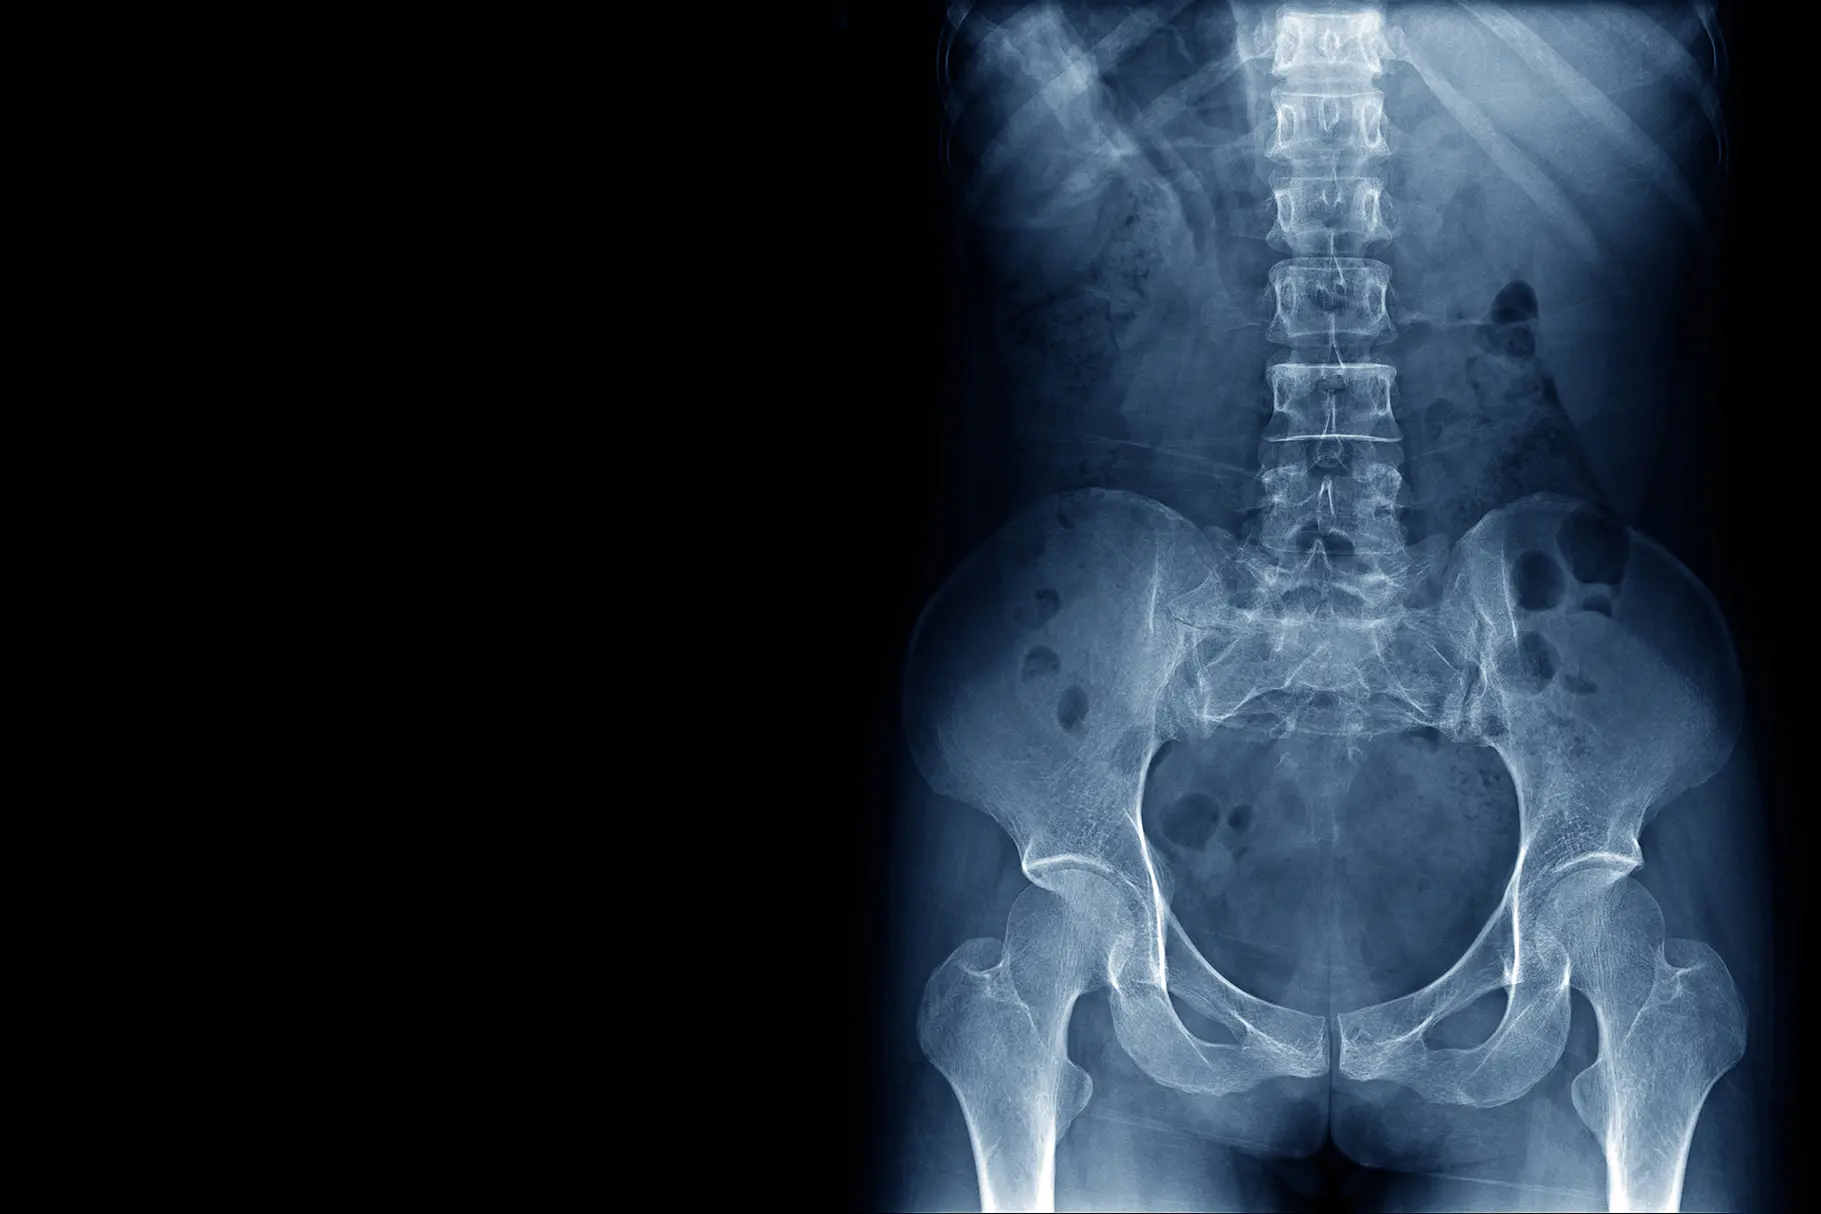

The electromagnetic spectrum includes X-rays, radiowaves, microwaves and visible light. X-rays have an extremely short wavelength, or high frequency, making them high energy. This means they can penetrate most materials. X-rays are used in medicine to examine the body ‘structure’. They are most useful for bones in the body but also show some soft tissue detail as well.

X-ray (radiography) is the most frequently performed radiology procedure. Canopy Imaging performs many thousands of these examinations each year.